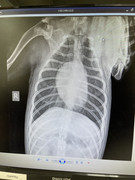

И в завершении на рентгене обнаружил внутри Акелло пневматическую пулю.

На УЗИ

Наталья